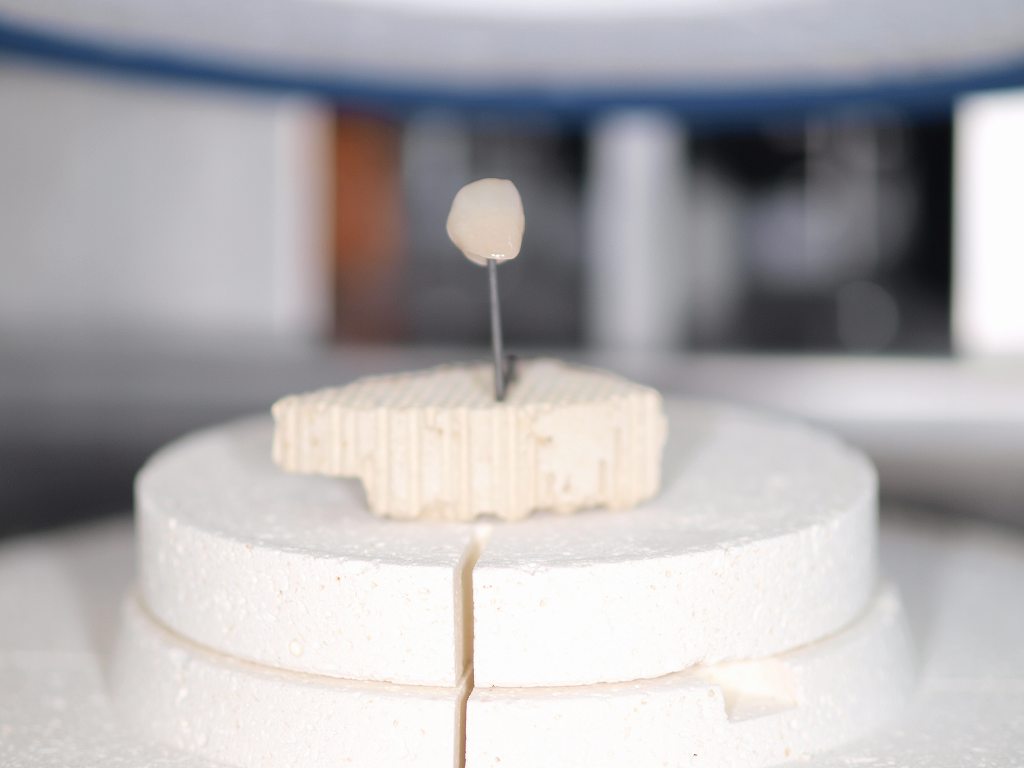

前歯部の作成はジルコニアフレームを使ったジルコニアクラウンというやり方とe-maxを使ったオールセラミッククラウンというやり方に分かれます。 強度はジルコニアフレームの方がありますが、複雑な工程を要しますので費用は2万円高く8万円となります。

前歯部の作成はジルコニアフレームを使ったジルコニアクラウンというやり方とe-maxを使ったオールセラミッククラウンというやり方に分かれます。 強度はジルコニアフレームの方がありますが、複雑な工程を要しますので費用は2万円高く8万円となります。